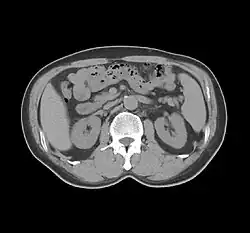

- Computed Tomography (CT). A non-invasive method to diagnose dorsal pancreatic agenesis by an absence of pancreatic tissue ventral to the splenic vein.[1]

Agenesis of dorsal pancreas has to be differentiated with pancreatic fat infiltration, chronic pancreatitis and atrophy of pancreatic body and tail.[4] The absence of pancreatic body and tail is the usual manifestation of dorsal pancreatic agenesis, the density and morphological features of the pancreatic head should be either normal or slightly enlarged due to compensation of the absent body and tail.[4]

Stomach/intestine sign can combine with CT for better diagnosis. Since dorsal pancreatic agenesis can be at times complicated with pancreatic tumors, CT is a visualisation tool that can be used to exclude both pancreatic tumors and abdominal tumors, which allows for improved observation.[1]